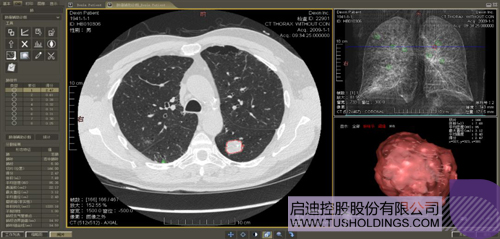

数字肺产品肺癌计算机辅助诊断

医疗影像智能分析是指运用人工智能技术、计算机视觉技术以及计算几何技术对医疗影像进行自动分析,帮助医生定位病症、分析、跟踪病情,并通过量化数据辅助医生做出诊断,目前其旗舰产品“数字肺”已经覆盖多种肺部疾病的早期检测、诊断、跟踪、术前规划等完整的医疗流程。在临床实践中,超过80%的医疗数据来自医疗影像,这些影像数据通常需要专业医生进行解读,工作的重复性高、效率偏低。如果能够运用智能影像分析技术,同时结合临床表现以及既往病例进行全面分析,那么就可以大幅度提升影像诊断效率和准确性,让专业医生的宝贵时间集中在复杂病情的诊断和治疗等环节。